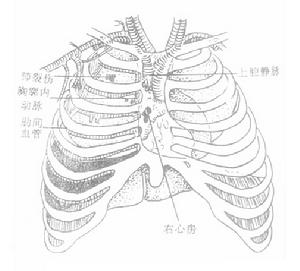

血胸的臨床表現隨出血量、出血速度、胸內器官創傷情況和傷員體質而差異。肋骨骨折並發少量血胸,一般失血量較少,臨床上不呈現明顯症狀。出血量多,超過1000ml,且出血速度快者,則呈現面色蒼白、脈搏快而弱、呼吸急促、血壓下降等低血容量休克症狀,以及胸膜腔大量積血壓迫肺和縱隔引致呼吸困難和缺氧等。小量血胸常無異常體徵。大量血胸則可呈現氣管、心臟向健側移位,傷側肋間隙飽滿,叩診呈實音。血、氣胸病例則上胸部呈鼓音,下胸部實音。呼吸音減弱或消失。由於肺撕裂而引起的血胸傷員常有咯血。積留在肋膈竇的小量血胸,胸部X線檢查可能不易被發現,或見到肋膈角消失。血胸量較多者,則顯現傷側胸部密度增大。在側臥位胸片上顯示比較清楚。大量血胸則顯示大片濃密的積液陰影和縱隔移位徵象。血、氣胸病例則顯示液平面。胸膜腔穿刺抽得血液則可確定診斷。血胸病人經穿刺抽血,胸膜腔積液減少後,可又增多。胸膜腔內血液凝固,穿刺未能抽出血液或僅能抽出少量血液,但休克症狀加重或X線檢查胸膜腔積液量增多;胸膜腔引流後每小時引流量超過200ml並持續2小時以上者,都提示有進行性出血,需及時處理。

血胸的臨床表現隨出血量、出血速度、胸內器官創傷情況和傷員體質而差異。肋骨骨折並發少量血胸,一般失血量較少,臨床上不呈現明顯症狀。出血量多,超過1000ml,且出血速度快者,則呈現面色蒼白、脈搏快而弱、呼吸急促、血壓下降等低血容量休克症狀,以及胸膜腔大量積血壓迫肺和縱隔引致呼吸困難和缺氧等。小量血胸常無異常體徵。大量血胸則可呈現氣管、心臟向健側移位,傷側肋間隙飽滿,叩診呈實音。血、氣胸病例則上胸部呈鼓音,下胸部實音。呼吸音減弱或消失。由於肺撕裂而引起的血胸傷員常有咯血。診斷鑑別